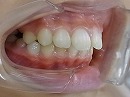

今回はt4kによって下顎後退症を改善している症例を御報告したいと思います。

下顎後退症 といっても多分聞きなれない病名だと思います。

一般的には出っ歯と言われていますが、この状態には2つのタイプがあります。

1、上顎の前歯の部分が成長しすぎているタイプ

2、下顎全体が後退しているタイプ

割合としては、下顎が後退しているタイプが殆どです。

トレーナーを使用して、後退している下顎を本来の位置に戻すために使用しています。

トレーナー使用中 使用開始時の状態

使用して5カ月後